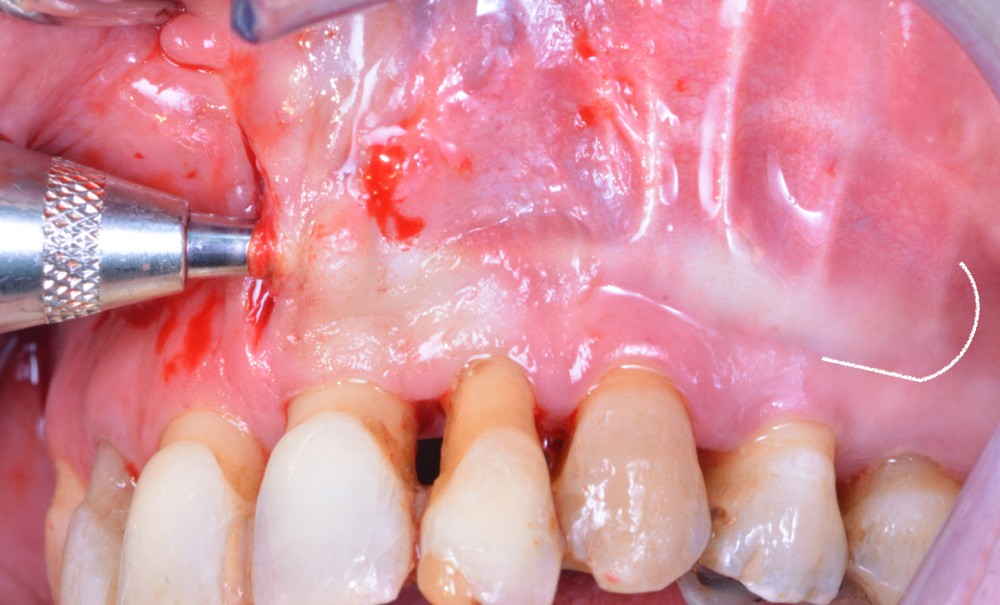

La régénération osseuse tunnelisée (ROT) illustrée dans cet article à travers deux cas cliniques est une régénération osseuse guidée (ROG) dont le protocole de mise en place diffère, avec pour objectif une moindre invasivité et une diminution du risque de complications.

La régénération osseuse tunnelisée (ROT) illustrée dans cet article n’est pas basée sur un changement de paradigme de la greffe osseuse. Il s’agit toujours d’une ROG, seul le protocole de mise en place diffère.